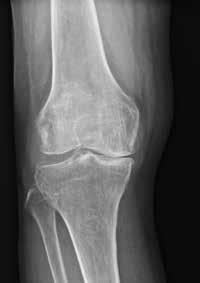

(Top, from left) X-ray images show a normal knee; unicompartment OA with some wearing on inner side of knee; and post-partial knee replacement.

(Bottom, from left)

Tricompartment OA with severe damage to both knees; and post-total knee replacement.

Not all bad knees need a total replacement of the joint. It is only when joint damage is very severe or complex that a total knee replacement (TKR) is likely. Otherwise, partial knee replacement (PKR) or knee preservation (KP) are options for those whose knees are less damaged.

Knee pain can be due to diseases like gout and rheumatoid arthritis, but is most often due to osteoarthritis (OA), where the protective cartilage that cushions the joints is worn down over time. OA is a significant health concern due to its impact on mobility and quality of life. Typically a disease of the elderly, OA is increasingly affecting younger

patients amid a rise in popularity of vigorous sporting activities.

In a healthy knee joint, cartilage and the gelatinous meniscus separate the femur (thigh bone) and tibia (shin bone). With wear and tear, the two layers are worn away. Walking and other movements cause

the femur and tibia to rub against each other, causing pain and inflammation.